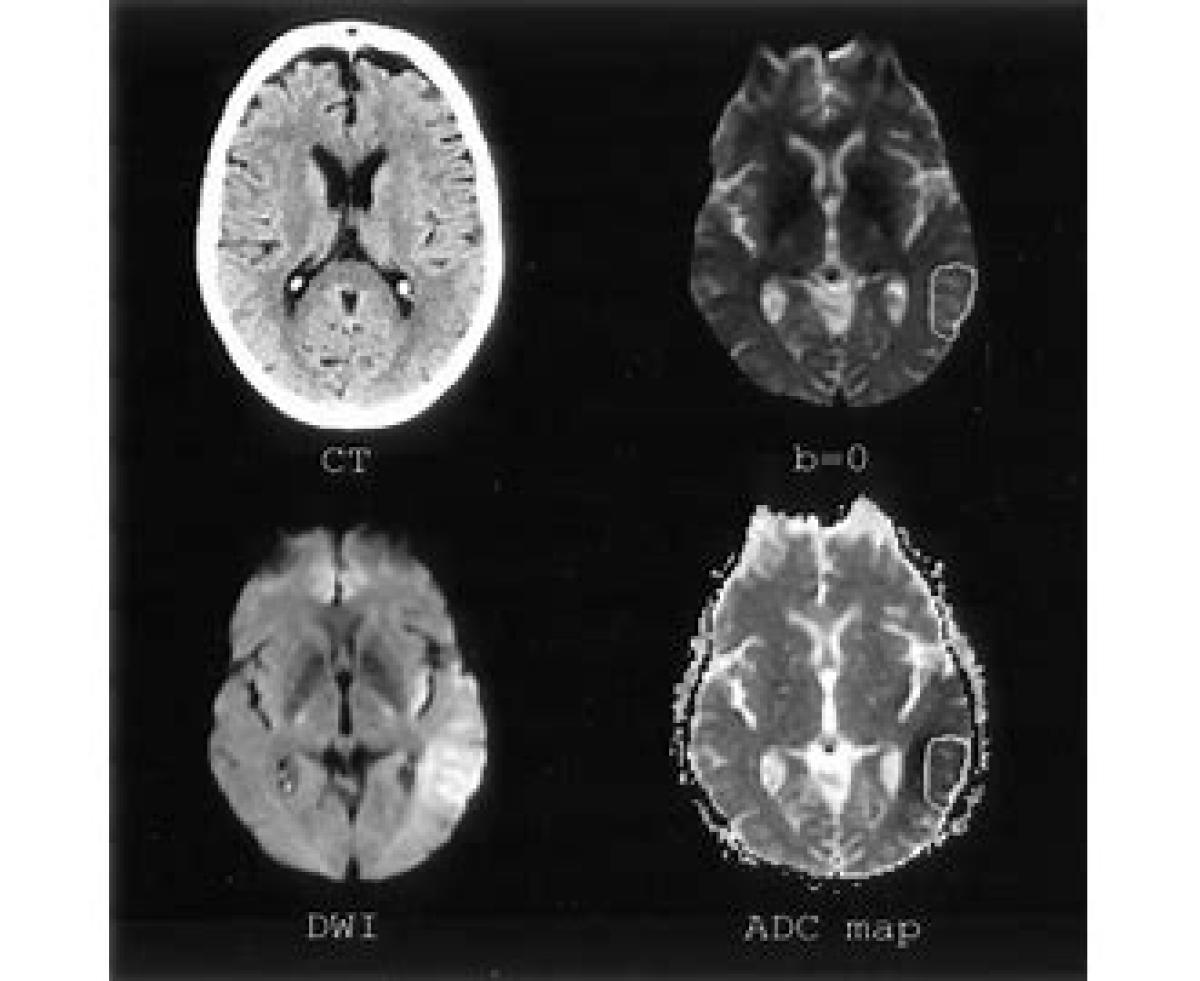

مخفف ADC Apparent Diffusion Coefficient ضریب پخش ظاهری یک کمیت در ام آر آی و بویژه در روش تصویرگیری پخش وزنی است، و با ADC نشان میدهند. این کمیت، برآیند جابجایی مولکولها را در یک بافت نشان میدهد. یک ارزش ADC بالا نشانگر حرکت زیاد و در نتیجه سیگنال ضعیف است.مشاهده نسخه کامل